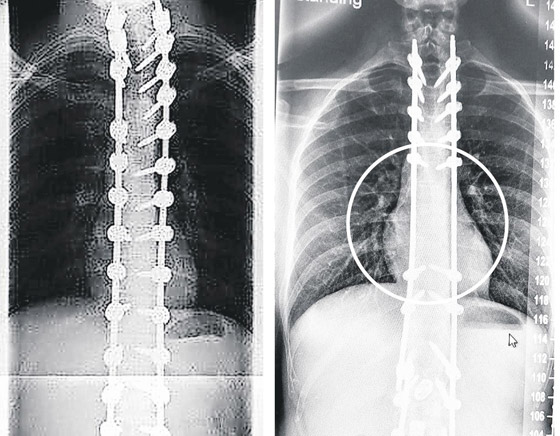

وفي حالة شارون سميث، استخدم ويليامسون مسامير أطول من اللازم في عمودها الفقري. وعُثر على أحدها بالقرب من الشريان الأورطي، وكان الآخر يلامس شرياناً منفصلاً. ولو انقطع، مثلما حدث لأوكونور، لكانت ماتت في ظرف ساعتين. وعاشت شارون مع المسامير لمدة عامين قبل أن يخضعها ويليامسون لعملية لإزالة أحدها، لكن الضرر الذي لحق بأنسجتها وأعصابها كان قد حدث بالفعل وهي تعيش عواقبه من حينها. وتقول: "انتهى بي الحال إلى إجراء ثلاث عمليات جراحية كان يفترض أن تكون واحدة. ولو تمت بشكل صحيح من البداية، لكانت حياتي مختلفة تماماً. أنا غاضبة جداً".

وفي حادث آخر، عام 2012، أصيب رجل بشلل وآلام حادة بعد أن أجرى له ويليامسون عملية جراحية بناء على مسح ضوئي انتهت صلاحيته منذ 29 شهراً، وهذا أدى إلى وضع مسامير العمود الفقري في غير مكانها الصحيح. وقال المريض، وهو الآن في الثلاثينيات من عمره، وطلب عدم الكشف عن هويته: "من الصعب جداً أن أقرأ هذا التقرير، بعد سنوات كثيرة جداً، لأعلم أنه كان ممكناً فعل الكثير لحمايتي، ومرضى آخرين كثر مثلي. لا يزال تأثير هذه الإخفاقات يؤثر بشكل كبير عليّ حتى الآن، بعد أكثر من عقد من الزمان، وأجد صعوبة بالغة في التعامل معها".